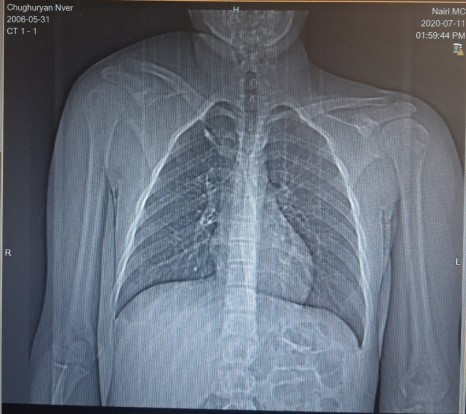

Նկար 1․ Թիակի ռադիոլոգիական պատկերը